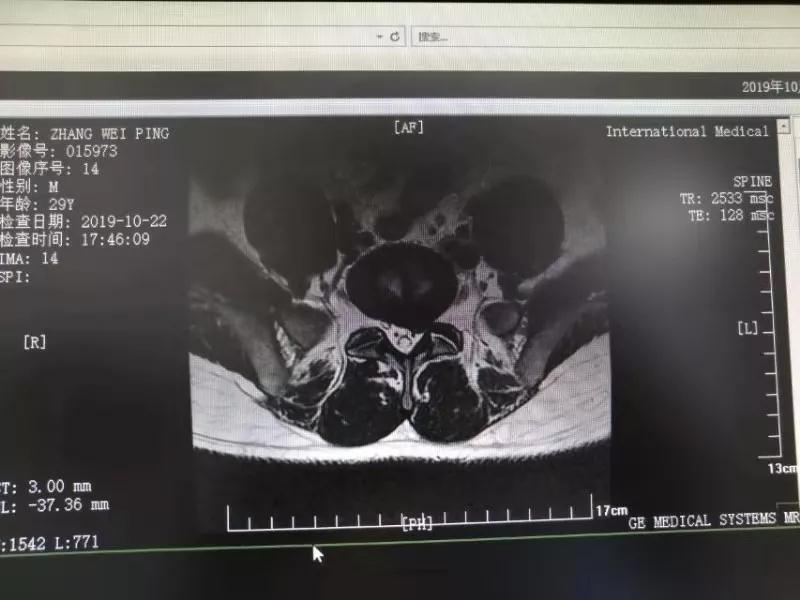

10月25日,29歲的患者小張了解到西安國際醫(yī)學(xué)中心骨科醫(yī)院專家云集,一大早便在家人的陪同下,來到西安國際醫(yī)學(xué)中心骨科醫(yī)院就診?!拔已闯掷m(xù)2年多,最近感冒后腰痛癥狀明顯加重了?!毙埫媛犊喑?,因?yàn)殚L期腰痛、左下肢放射性疼痛,她晚上睡覺不能平躺,經(jīng)常疼得睡不著,需要口服止痛藥物才能有所緩解。走路走不了多遠(yuǎn)就開始腿抽的疼,嚴(yán)重影響到工作和生活。

結(jié)合患者的檢查以及年齡情況,王自立副院長推薦讓專門研究椎間孔鏡技術(shù)王雄勛主任給小張做微創(chuàng)的椎間孔鏡手術(shù)。該手術(shù)創(chuàng)傷很小,不影響脊柱的穩(wěn)定性,尤其適合于椎間盤突出的年輕患者,懷著對骨科醫(yī)院專家的信任,小張與家人商議后,接受手術(shù)治療。